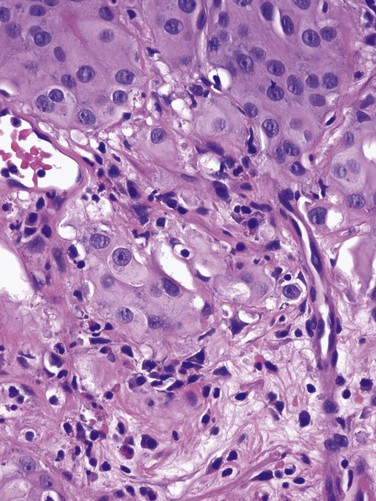

The demarcation between “superficial” and “invasive” has sometimes been errantly considered between T1 and T2. However, T1 tumors invade the lamina propria by definition, so they cannot be accurately characterized as “noninvasive.” Unlike the urothelium, which is devoid of vessels or lymphatics, the lamina propria is rich in both, providing opportunity for metastasis. These tumors sometimes invade the wispy and discontinuous muscularis mucosae of the lamina propria, which can be confused for muscularis propria (detrusor) during pathologic interpretation. Imprecise verbiage on the pathology report can lead the urologist to misinterpret invasion of muscularis mucosae to be “muscle invasive,” risking overstaging error. Direct communication between urologist and pathologist when this occurs is essential.

Deep lamina propria invasion carries a substantially more serious prognosis in some reports, and some have proposed these be subcategorized as T1b (Younes et al, 1990). However, the value of substaging has not been validated in other studies, so the 1998 Bladder Cancer Consensus Conference Committee rejected the concept (Platz et al, 1996; Epstein et al, 1998).

T1 tumors are usually papillary; a nodular or sessile appearance suggests deeper invasion. Deep penetration into the lamina propria, especially if involving muscularis mucosae, increases the risk of recurrence and progression in some reports. Lymphovascular invasion increases the risk as well (Lotan et al, 2005). Hydronephrosis usually indicates muscle invasion.